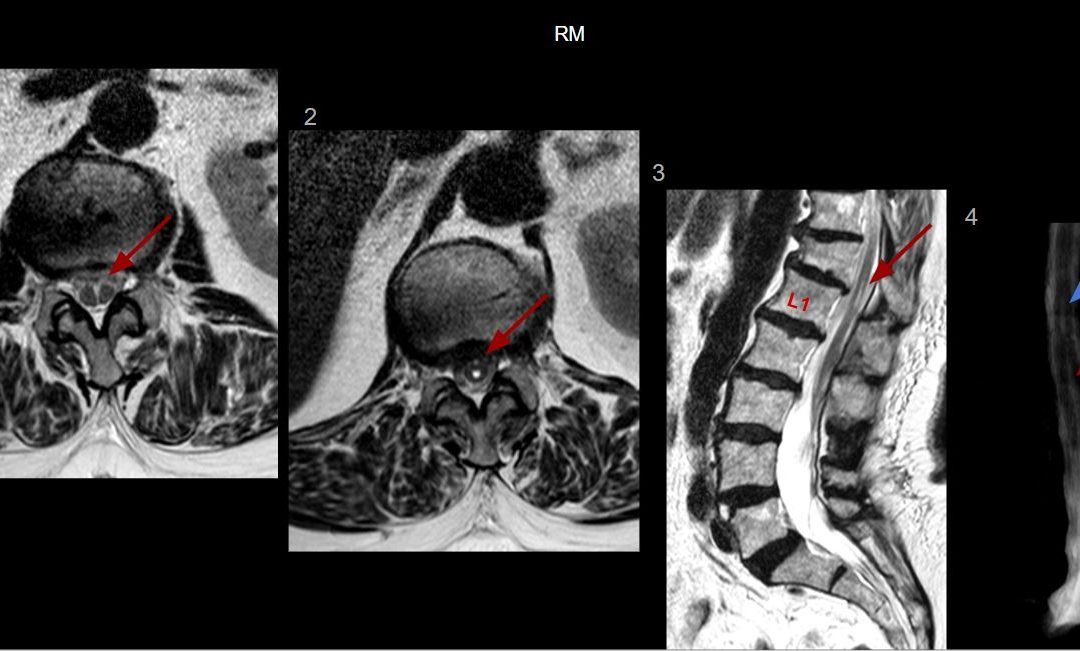

Resonancia magnética: secuencias ponderadas en T1 con gadolinio en plano axial (A), sagital (B) y coronal (C): Masa extraaxial de aspecto heterogéneo, bien definida, con un intenso realce periférico, de 42 x 41 x 38 mm (AP x TR x CC) en la línea media frontobasal. La lesión está en contacto con la lámina cribiforme y parece originarse del bulbo y tracto olfatorio izquierdo. Aisladas formaciones quísticas periféricas. Secuencia ponderada en T2 plano coronal (D): extensa área de hiperseñal T2 que se extiende por la sustancia blanca del lóbulo frontal izquierdo.